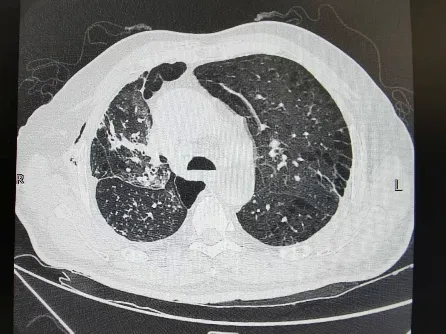

术前肺CT

放射科专家分析影像资料后指出,患者右胸巨大直径约8cm,占据右侧胸腔55%,且与肺门血管、胸膜存在多处粘连,术前需标记粘连位置,避免术中损伤血管;左胸术后残余胸膜增厚,可能增加肺复张难度。通过三维重建影像,清晰呈现病灶与周围组织的解剖关系,为手术精准操作提供关键依据。

呼吸科专家则聚焦肺功能评估:患者长期吸烟史导致肺功能中度受损,FEV1(第一秒用力呼气容积)仅为预计值的62%。术前需通过雾化吸入支气管扩张剂改善通气,同时指导腹式呼吸训练,提升术后呼吸耐受度;术后需警惕肺部感染与肺不张风险,建议提前制定抗感染与呼吸康复方案。